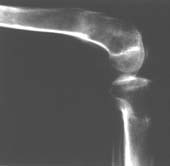

Пациент В. 53 лет, травма в феврале 2009. ДЗ. Открытый оскольчатый перелом нижней трети голени. При боли поступлении выполено ПХО, аппарат Илизарова. В последующем проводили ВХО, резекция костных отломков, укорочение 6 см, рана зажила. Была выполнена остеотомия большеберцовой кости в проксимальном отделе, резекция. Производилось тракция. На последних рентгенограммах выявлено, что одновременно с "выращиванием" регенерата произошло низведение надколенника на длину выращенного регенерата. Клинически: активное разгибание сохранено, объем движений в колене 180-110 градусов. Черными стрелками обозначен верхний край надколенника с одной и с другой стороны. Красная стрелка обозначает пальпируемую связку надколенника. Причина - остеотомия выше места прикрепления связки надколенника. Вопрос: была ли у кого подобная ситуация? Что делать? При первом обдумывании приходит решение: отсечение места прикрепления связки надколенника с костным блоком, перемещение на "правильное" место, укорочение сухожилия четырехглавой мышцы.

К сожалению, подобное осложнение "нет-нет да и возникает" при удлинении, коррекции деформации голени. В англоязычной литературе оно описано как "patella baja". Один из вариантов лечения - проксимальное перемещение надколенника приемами чрескостного остеосинтеза.

По-моему, надколенник низвелся на величину, гораздо меньшую удлинению.